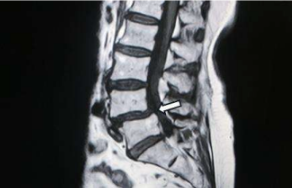

此症狀主要是固定脊椎上下節之小面關節鬆動無法有效穩定脊柱,因此當脊椎上下節逐漸脫位而壓迫到脊椎間神經根而有坐骨神經痛的症狀。在久站、久走或上半身前彎坐姿一段時間後容易誘發症狀 (Wiltse, 1976: 23-29; $\text{Meyerd-ing, 1956:566-591; Fitzgerald, 1976:184-192; Liu, 2017: 41-47; Smorgick, 2014:e260-e264)。(參見圖 3)

圖 3 第四、五節腰椎滑脫(如箭頭所示)